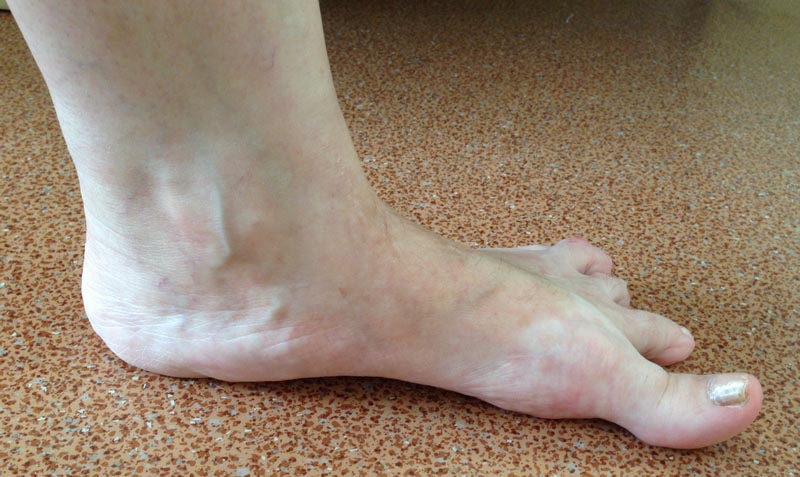

Пциентка Н, 58 лет. Больна с 2005г. Лечилась консервативно. Со слов, тогда было сильное искривление 1,2,3,4 пальцев в латеральную сторону.

В 2012г. операция: коррекция деформаций 1,2,3, 4 пальцев.Рецидив. В 2013г. – коррекция деформации 2,3,4 пальцев. С ноября 2014г. рецидив деформации 1,2,3,4 пальцев. Возможные варианты коррекции?

А что беспокоит пациентку? Есть ли натоптыши на подошве? Болит ли первый плюснефаланговый сустав? Или еще где болит? Лечим ведь пациента, а не деформацию. Если же исходить из имеющихся данных и отсутствия информации о ранее выполненных операциях, то необходимо выполнить обратную остеотомию Akin, чтобы устранить hallux varus; укорачивающие остеотомии 1-4 плюсневых костей (первой - для декомпрессии первого плюснефалангового сустава, поскольку имеются признаки его тугоподвижности - установка основной фаланги в положении подошвенного сгибания, а также hallux hyperextensus. Второй-четвертой плюсневых для того, чтобы легче было устранить отклонение кнаружи соответствующих пальцев). Остеотомии (дистальные) 2-4 плюсневых лучше не фиксировать. И выполнить остеотомии оснований основных фаланг 2-4 пальцев, которые зафиксировать на 4-5 недель повязкой в нужном положении, не прибегая к остеосинтезу. Конечно, оптимальным в подобном случае является чрескожный метод (выполнение остеотомий через проколы кожи).